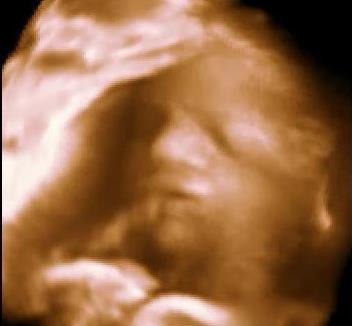

. Meen fortalte hende at jeg havde været til 3d scanning og da målte hun ham til ca. at veje 1600 g (d. 18 nov), så han burde veje lidt mere nu.. Men igen det er jo svært at sige med sikkerhed hvad de små vejer